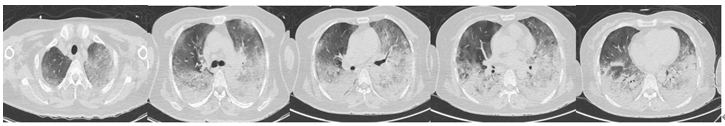

Case 5

患者,男,30岁,代主诉:高处坠落致腰背部疼痛18小时,2021年4月18日入院。“高血压”多年,未予特殊治疗。入院诊断:重型闭合性颅脑损伤,脑挫裂伤,蛛网膜下腔出血,等。术后发热,予腰穿,留取脑脊液监测及mNGS,结果提示人葡萄球菌(序列数3),予以美罗培南(2.0 g q8h)+利奈唑胺(0.6 g q12h),腰大池持续引流,最终患者预后良好。

图片